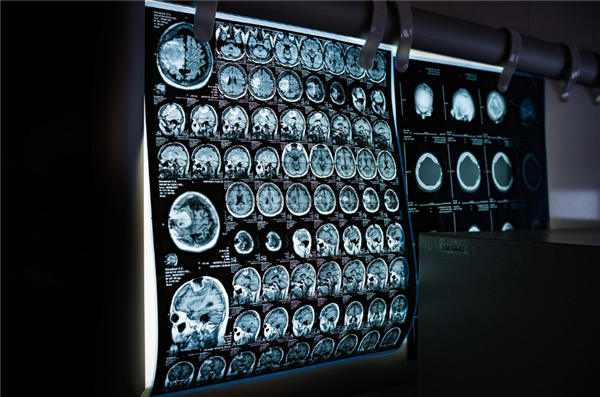

市民黄女士的接诊医师也深有感触,“通过广东影像云平台调阅影像来诊断,精准度也比传统胶片更高。患者带来的胶片有时看不清楚,在电脑上打开的电子影像可以清晰看到更多细节,还方便放大缩小等操作”。